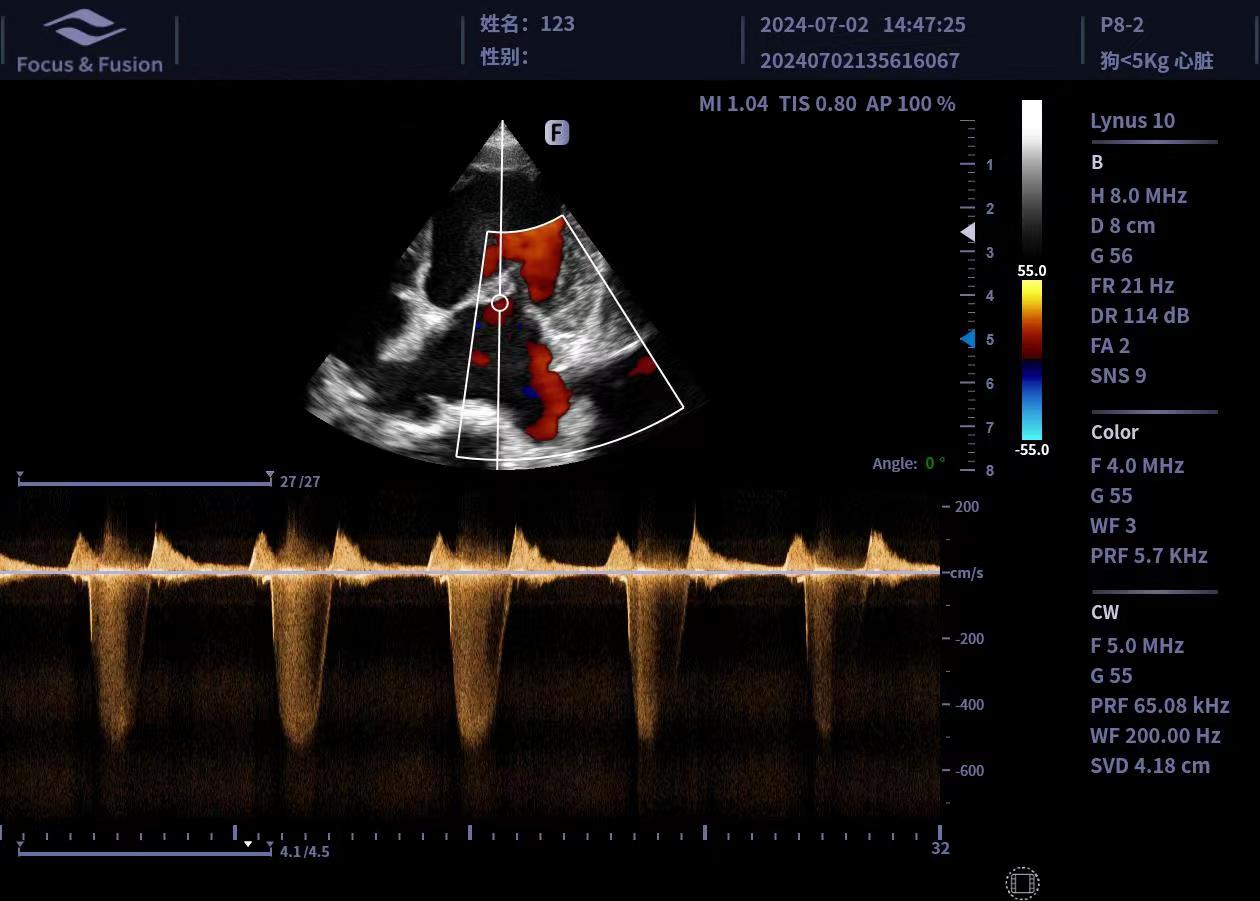

圖片展示

Image List